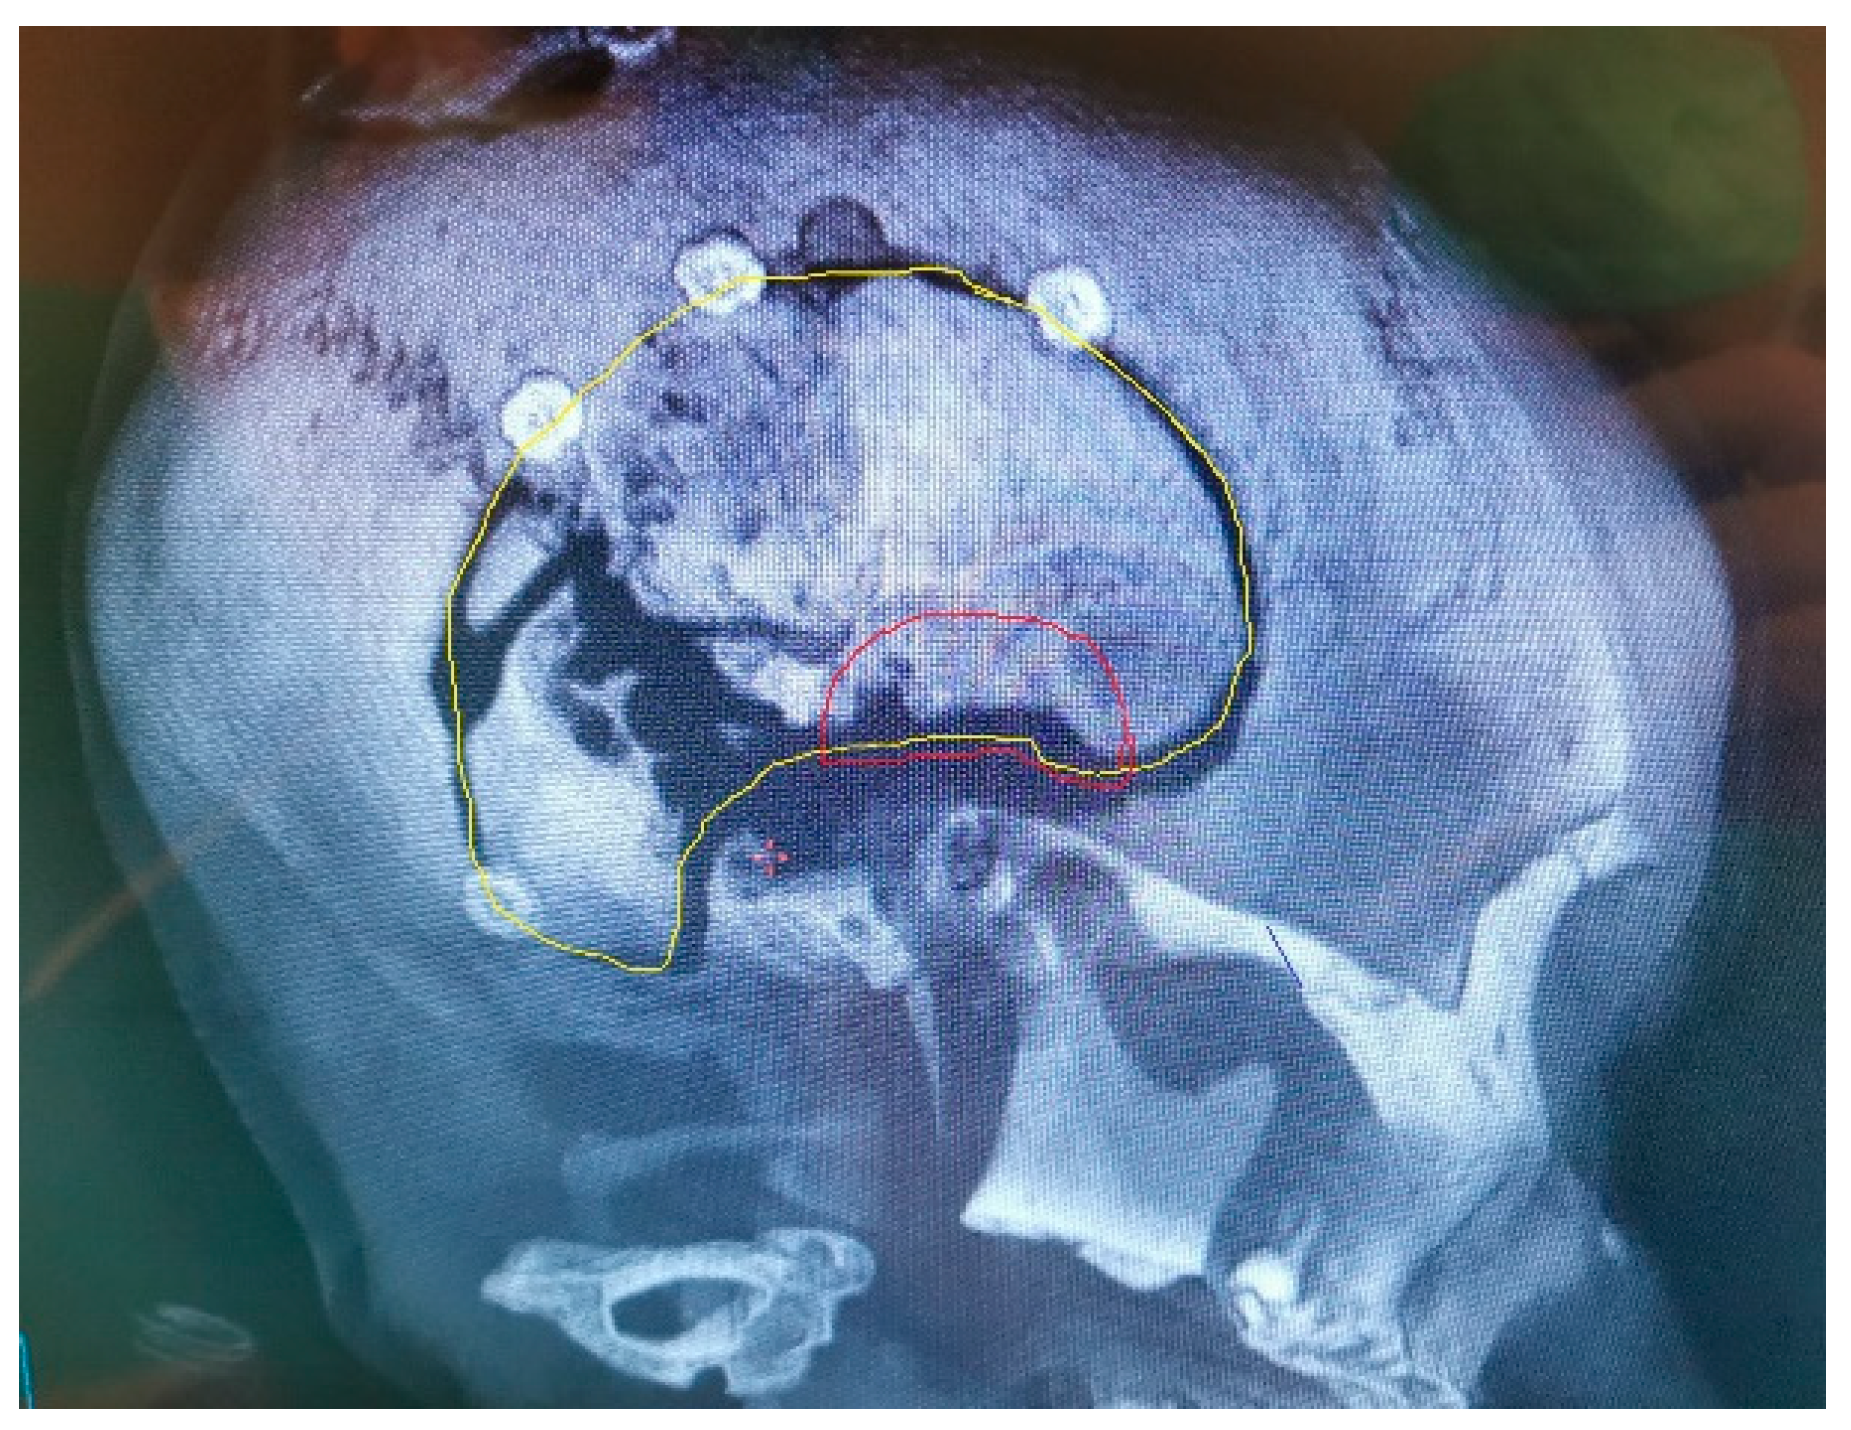

The artificial bone flaps made of titanium, PEEK and porcelain are custom-made in advance of the implantation. Before the operation, an accurate CT scan of the head is needed to manufacture a three-dimensional model for artificial flap manufacturing [83,84,85]. The CT scan is performed with 1 mm slices and with no gantry, ensuring that the flap, once produced, is completely compatible with the bone defect in the patient’s skull (Figure 6). One disadvantage is that the artificial bone flaps lack osteoinductive or osteogenic properties. Their production may take weeks before being delivered to the clinical department and it is not very available. Moreover, these products are very expensive and their production needs to be planned well in advance, according to the shape of the bone defect [72,77,81,82,83,84,85].

Figure 6. The tumour invades the cranial bone. This part will be removed during surgery. For the reconstruction, one alternative also includes PEEK, which is very popular for artificial flap manufacturing. The 3D reconstruction needs to be performed before the manufacturing of such PEEK implant. The safety margin of resection is included in the planning, providing enough space for diseased bone removal and proving a good fit.